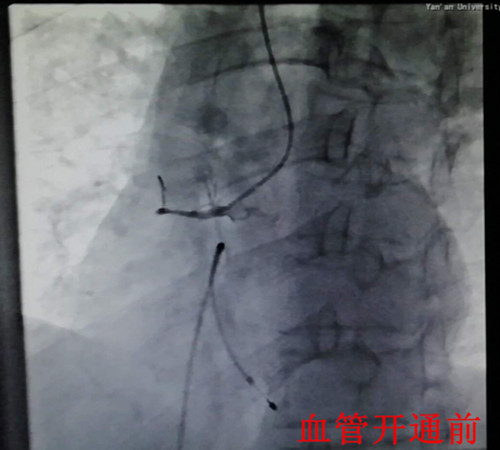

在一阵有效地抢救之后,患者在气管插管、呼吸机辅助呼吸下,先行心脏临时起搏器置入,后行左右冠状动脉造影,造影显示:右冠状动脉呈鼠尾状,开口5mm处100%闭塞,旋支血管中远段60—99%弥漫狭窄病变。手术者立即开通右冠状动脉,尽管患者在手术过程中不断出现室速室颤,血压下降,但随着右冠状动脉远端血流恢复,患者终于生命体征趋于平稳,安全返回监护室继续下一步治疗。